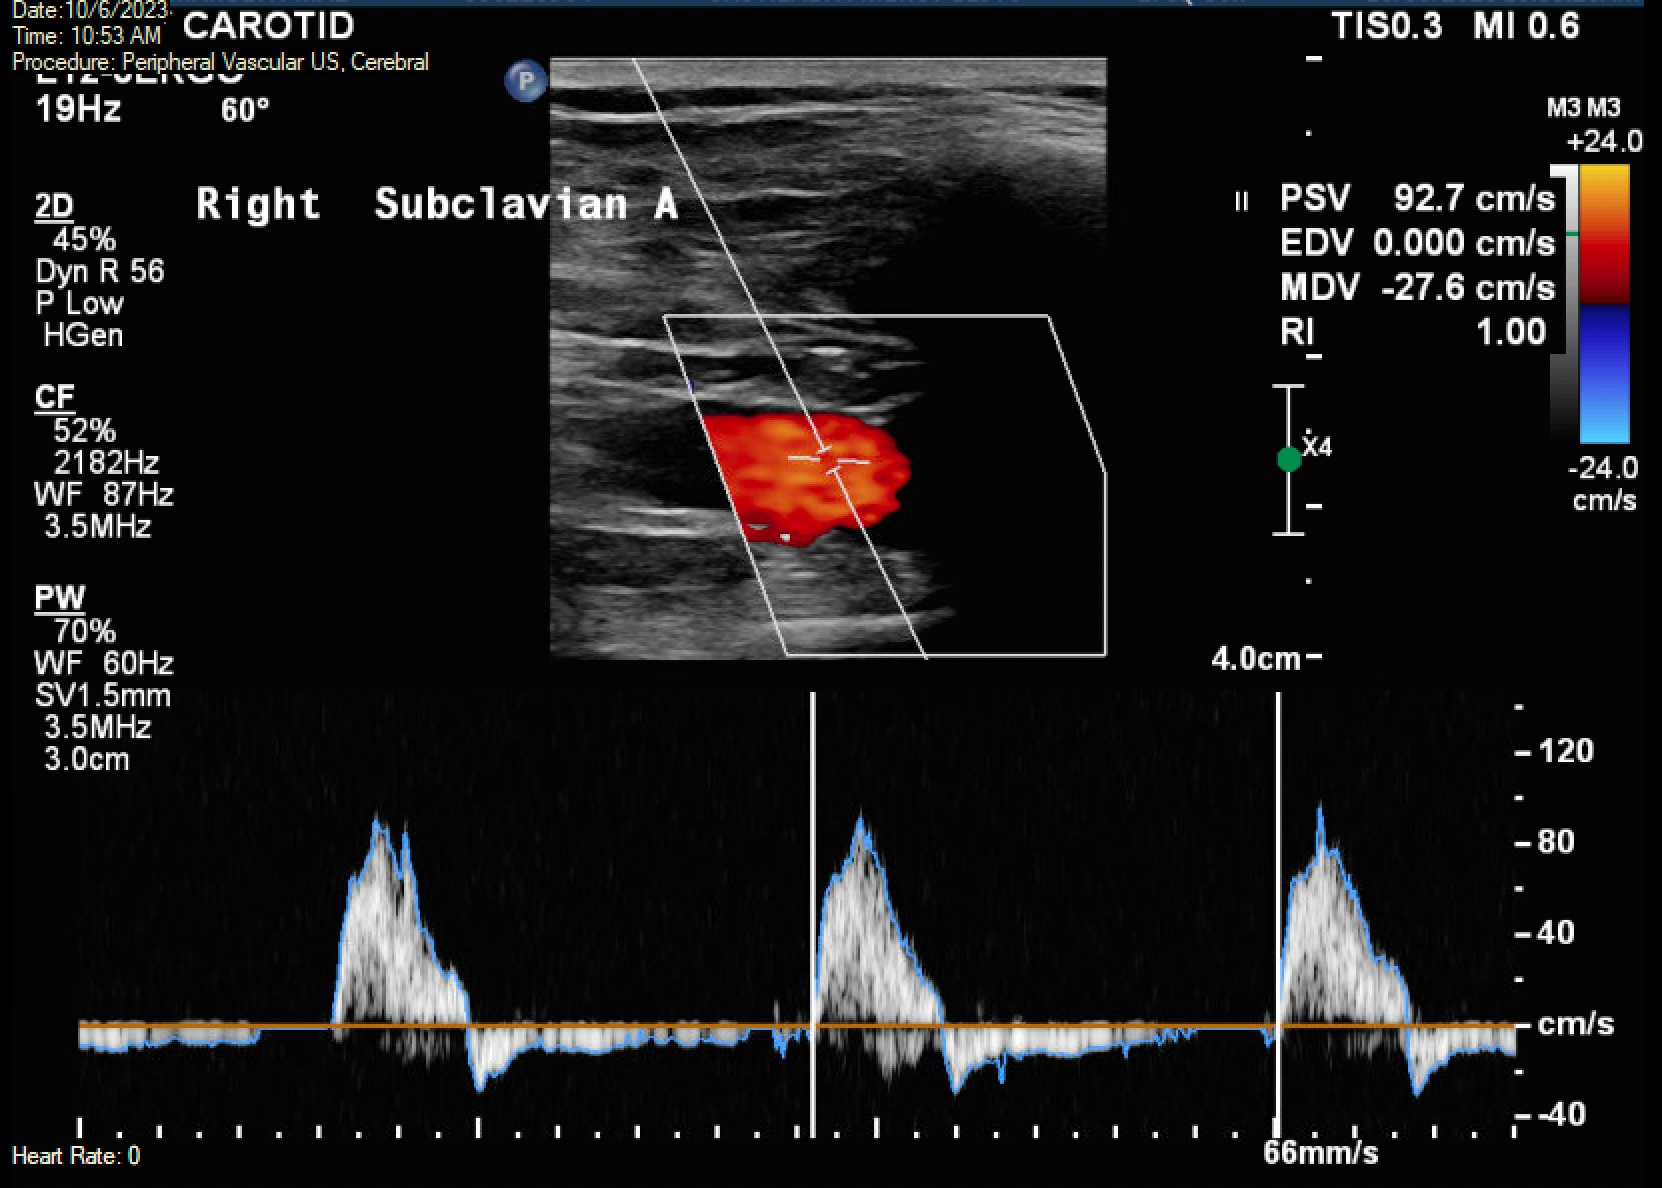

Innominate artery disease exposes patients to the risk of various events affecting both the posterior fossa and hemispheric region, such as vertebrobasilar insufficiency, amaurosis fugax, and stroke.5 Numerous studies have illustrated that severe lesions in the innominate artery significantly disrupt the flow in the right vertebral artery compared with that in the right carotid artery.3,6 In cases of innominate artery occlusion, the flow is diverted from the basilar axis through the right vertebral artery into the subclavian artery, where it retrogradely enters the right common carotid artery and then moves cephalad.4 Doppler findings may reveal midsystolic decelerations and elevated ratios of peak systolic velocity between the left common carotid artery and the right common carotid artery in cases of innominate artery disease, although the severity of stenosis does not consistently correspond to these duplex findings.

During a follow-up appointment 1 month later, the patient reported no dizziness, fainting, or near-fainting episodes, TIA, or stroke-like symptoms. Her right arm heaviness and numbness were resolved completely and she had a strong radial pulse bilaterally. A carotid and subclavian Doppler examination was scheduled for 6 months post-procedure to assess the condition of the stent. This showed multiphasic waveforms in both subclavian arteries with mild disease in the right carotid artery and the previous left subclavian stent without any elevated velocities or evidence of stenosis in the right innominate or subclavian arteries. (Figure 7).